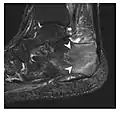

Fatigue fractures are more frequent in women which may be due to the relatively smaller bones of women. Moreover, pregnancy is a well-recognized risk factor for femoral neck fatigue fracture. While fibular and metatarsal fractures have a low risk of complications, other sites including the femoral neck, midanterior tibia, navicular, talar, and other intraarticular fractures are prone to complications such as delayed union, nonunion, and displacement. The site of the insufficiency fracture may be specific to the activity: for example, rugby and basketball players are more prone to navicular fractures, while gymnasts have a higher risk for talar fractures (Figure 7). Long distance runners are at increased risk for pelvic, tibial (Figures 8 and 9), and fibular fractures. In the military, calcaneus (Figure 10) and metatarsals are the most commonly cited injuries, especially in new recruits. Billiard players are at risk for upper limb fractures (Figure 11).[1]

a

b

Figure 10: Calcaneal fatigue fracture in a 30-year-old male runner. Radiographs were normal (not shown). (a) Sagittal T1-weighted and (b) short tau inversion recovery images show a linear hypointensity (arrows) of calcaneal tuberosity within diffuse bone marrow edema, which appears as an ill-defined area of hyperintensity on a fluid sensitive pulse sequence (arrowheads).[1]